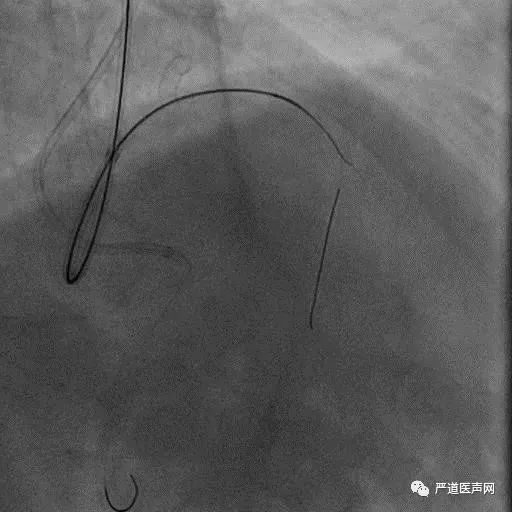

Case 1: Male 66 yrs, first attempt failed in local hospital

7F EBU 3.5, 6F SAL 1.0

• Stump

• Lesion length > 20 mm

• Absence calcification

• Promising landing zone

• Tortuosity epicardial CC

XT R KDL Parallel wiring UB3

Corsair Not Crossboss!

Stingray LP

Stick with GAIA Third

Final Results